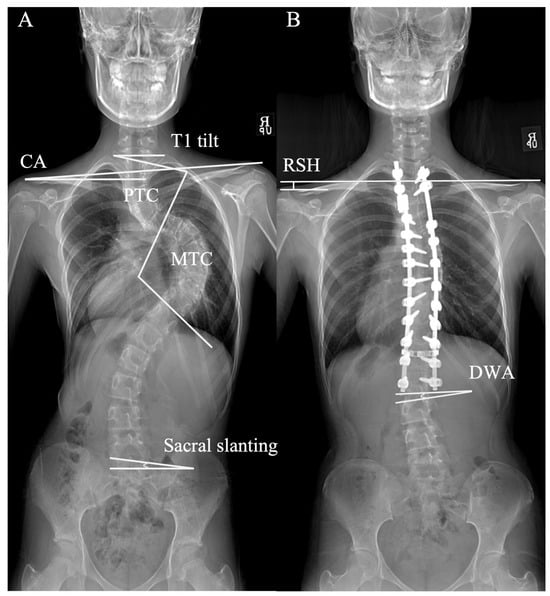

2.2. Demographic and Radiographic Measurements

| DWA | Distal Wedge Angle |

| PSI | Postoperative Shoulder Imbalance |

| RSH | Radiologic Shoulder Height |

| PTC | Proximal Thoracic Curve |

| MTC | Main Thoracic Curve |